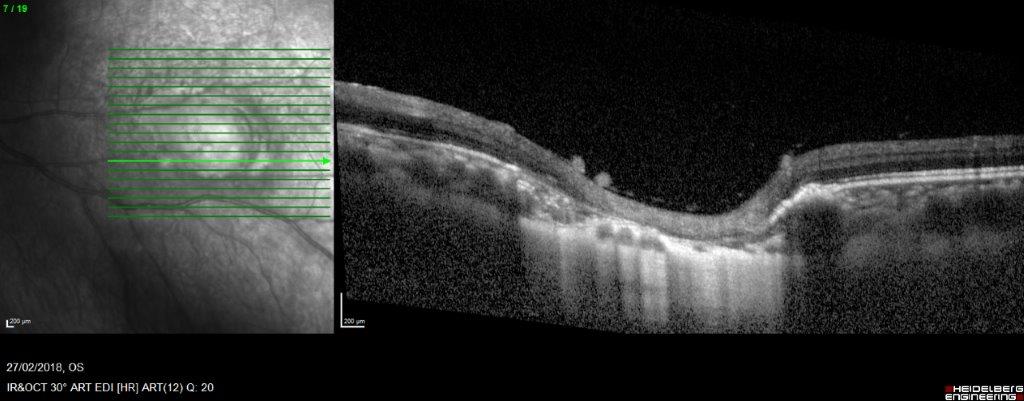

Multimodal imaging and laboratory investigations can assist in diagnosis, especially in atypical cases. In particular, optical coherence tomography (OCT) can assist in early diagnosis while waiting for laboratory results. OCT morphologic features have been validated in various case series (Table 1; Fig 3 & 4)3.

Fig 3. OCT imaging of active toxoplasma retinochoroiditis showing disruption of retinal layers, retinal thickening, retinal hyperreflectivity, RPE elevation, focal choroidal thickening, choroidal hyporeflectivity, hyaloid thickening, hyperreflective round shaped deposits along the posterior hyaloid, retrohyaloid hyperreflective spots, cavernous retinitis